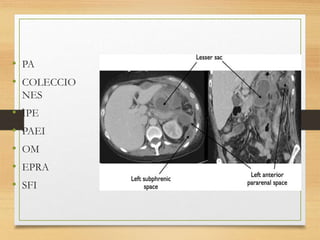

• PA

• COLECCIO

NES

• IPE

• PAEI

• OM

• EPRA

• SFI

• PA • COLECCIO NES •IPE • PAEI • OM • EPRA • SFI